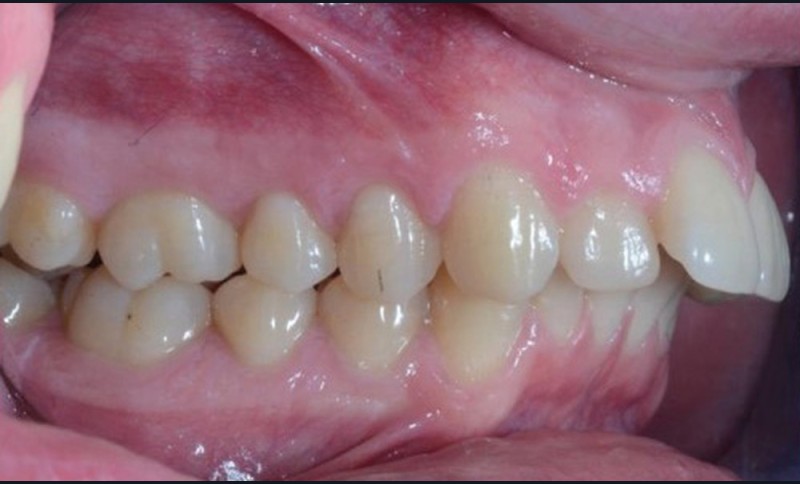

C’est à ces questions que nous permettront de répondre les deux premiers conférenciers, parodontologistes : le Dr Béatrice Straub nous présentera le renfort parodontal minéralisé, technique qu’elle a développée et pratique depuis de nombreuses années, pour éviter les préjudices des mouvements orthodontiques à risque, notamment lors des décompensations préchirurgicales (fig. 1a-d) ; le Pr Anton Sculean abordera le thème des greffes, avec leurs indications, les différentes techniques à privilégier et illustrera ses propos par de nombreux cas cliniques aux résultats esthétiques impressionnants.